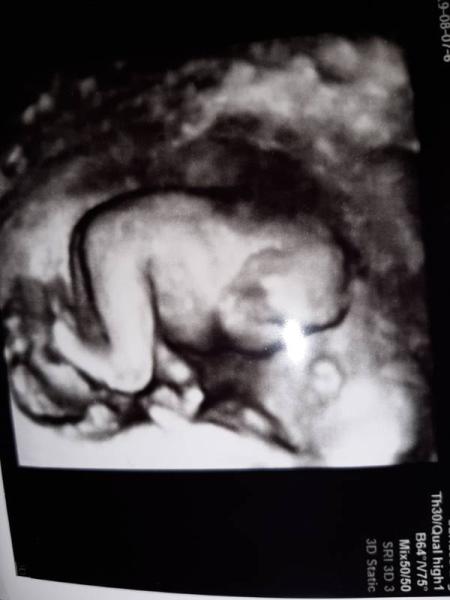

Ich wollte euch nur mal mein Glück mitteilen und zwar hat mein FA vor 2 Wochen gemeint einen schnippi gesehen zu haben! Da wir schon 2 jungs haben muss ich ehrlich sagen waren wir erst etwas enttäuscht ! Wir befinden uns z.z im Sommer Urlaub vor 2 Tagen bekam ich heftige Krämpfe um sicher zu gehen das mit dem baby alles in Ordnung ist sind wir in eine Klinik gefahren! Es war zum Glück alles gut nur eine leichte lebensmittelvergiftung ! Der Arzt hat 3 mal geschaut und ist sich zu 100 % sicher das es diesmal ein mädchen wird ! Wir konnten es erst gar nicht glauben und sind super happy hoffentlich bestätigt es mein FA am Dienstag zurück in Deutschland!!

Bild zu ÜBERGLÜCKLICH - Forum für Januar - Mamis

Ich erinnere mich. Das Foto, welches Du gezeigt hast, war eindeutig Junge. Sehr merkwürdig. Da bin ich echt gespannt. Lese ja noch oft bei Euch mit, so aus Jan. 19. Bei uns sah es nach 2 Mädchen exakt so aus und da ist dann auch nichts mehr abgefallen, was gut so ist!!! Jungs sind toll

Klar! Wir waren da such immer sehr verwöhnt Je in der 16. Woche gab es ein 100 % Outing, was dann auch so war. Und eben weil wir beim Jungen genauso ein Foto hatten, war ich mir so sicher als du es gezeigt hast Schönen Urlaub noch!